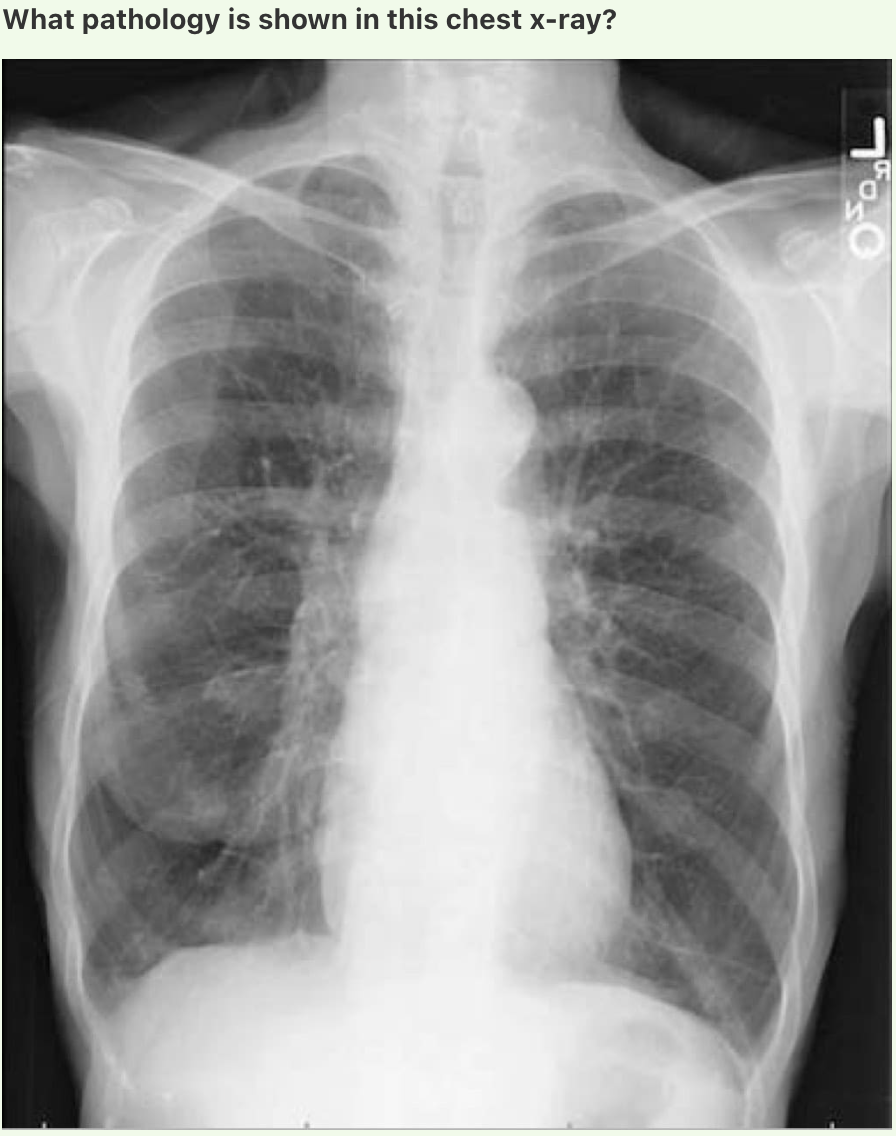

What pathology is shown in this chest x-ray?

• A ) Chronic obstructive pulmonary disease

• B ) Lung cancer

• C ) Normal

• D ) Pleural effusion

• E ) Pneumonia

• F ) Pneumothorax

• G ) Pulmonary oedema

• H ) Tuberculosis

A

Answer: Pulmonary oedema